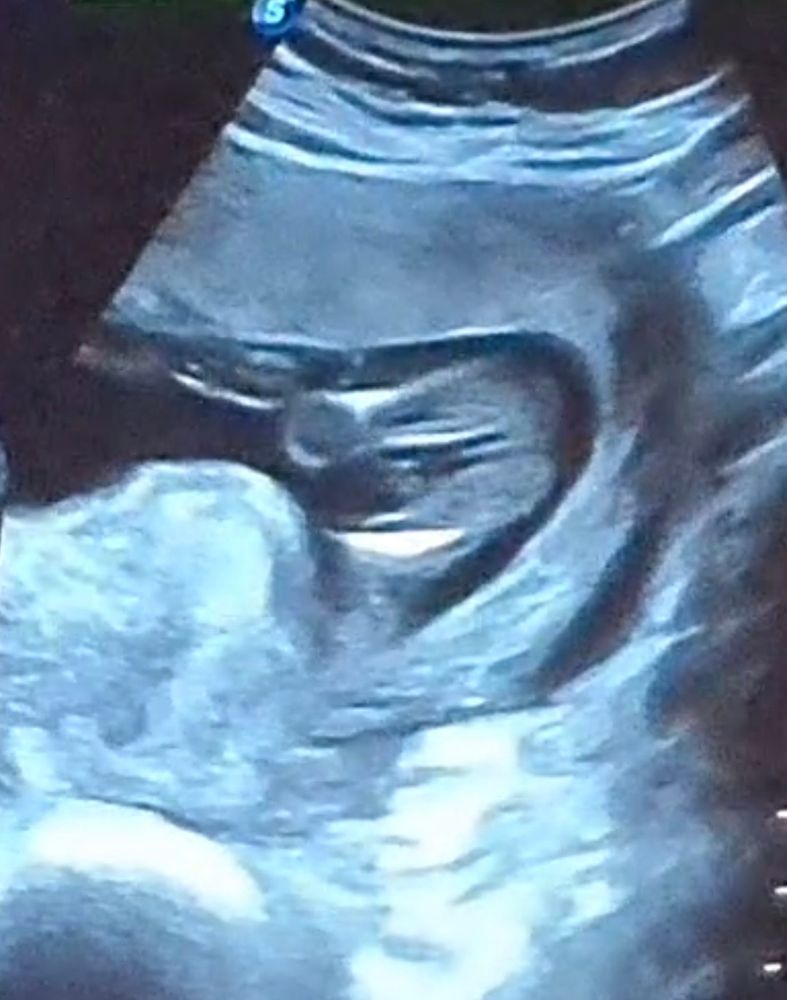

Ой, да, у вас тоже очевидно, что девчуля😍 Поздравляю!)

Ravlik, спасибо! Я еще на первом скрининге увидела, что между ножек нет ничего. И вчера на узи, врач смотрела со всех сторон и по животу и внутри, когда шейку измеряла и дала прям 100%гарантию.